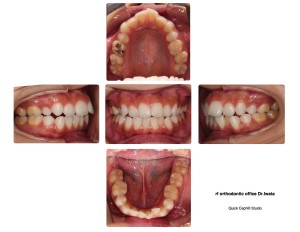

経過の写真を載せます。

【スタート前】

【インビザライン6枚目】

下前歯のガタガタした歯が少しほぐれてきました。嬉しい!!